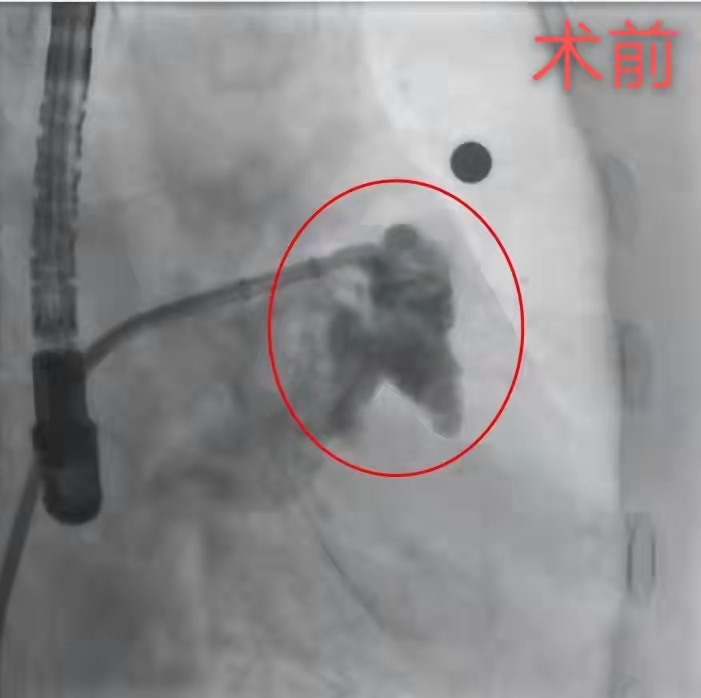

术前造影显示左心耳内分流形态